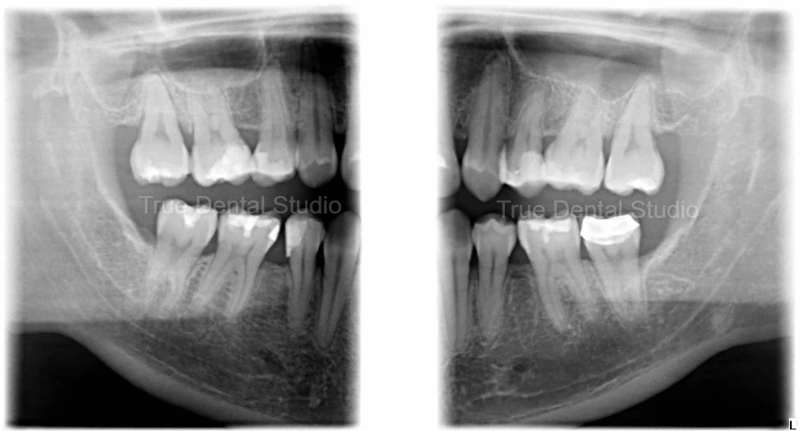

Bitewing X-Ray image of patient's teeth.

Case 2: Patient B underwent bitewing X-Ray imaging prior to receiving dental scaling and polishing treatment. The patient reported experiencing sensitivity in the molar regions, prompting further diagnostic evaluation.